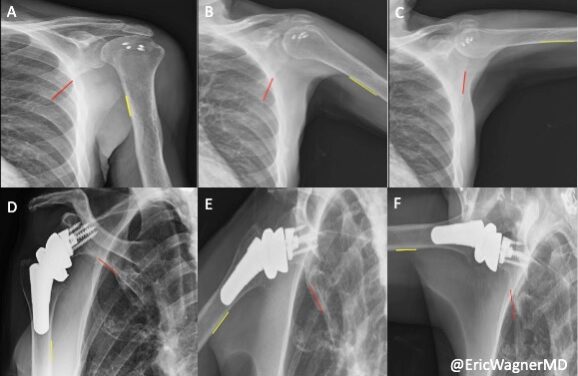

X-Ray Imaging Technique Helps Decide Best Surgery for Rotator Cuff Tears

The low-dose X-ray technique shows how shoulder mobility differs after two surgeries, giving doctors new data to guide treatment decisions.